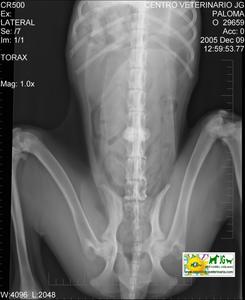

Radiografía con contrastes: mielografía por saco dural | |||||||||

![]() por Juan M. Griñán. Veterinario ![]() comparativa entre una mielografía (mostrando la aguja) y una resonancia magnética, secuencia SE T1w (mostrando donde está el saco dural, sitio para la inyección del contraste). Nótese la extravasación del contraste yodado en la mielografía. | |||||||||